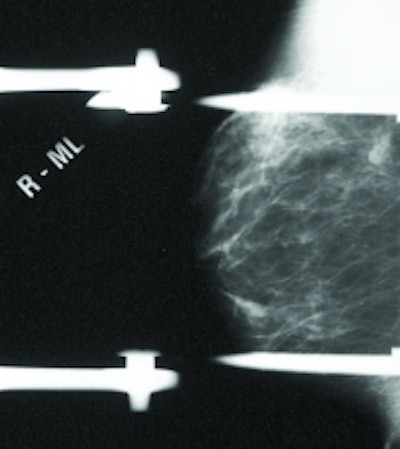

Patient is a 51-year-old female with prior left-breast lumpectomy of infiltrating ductal and DCIS. Mammogram (left) indicated nodular density in right breast, stable for three years. No abnormality detected, BI-RADS 2. Scintimammography with Dilon 6800 system (right) revealed area of high-density 6-mm focal uptake. Histopathology results indicate right breast intraductal and infiltrating ductal with DCIS carcinoma. Sentinel node was negative.